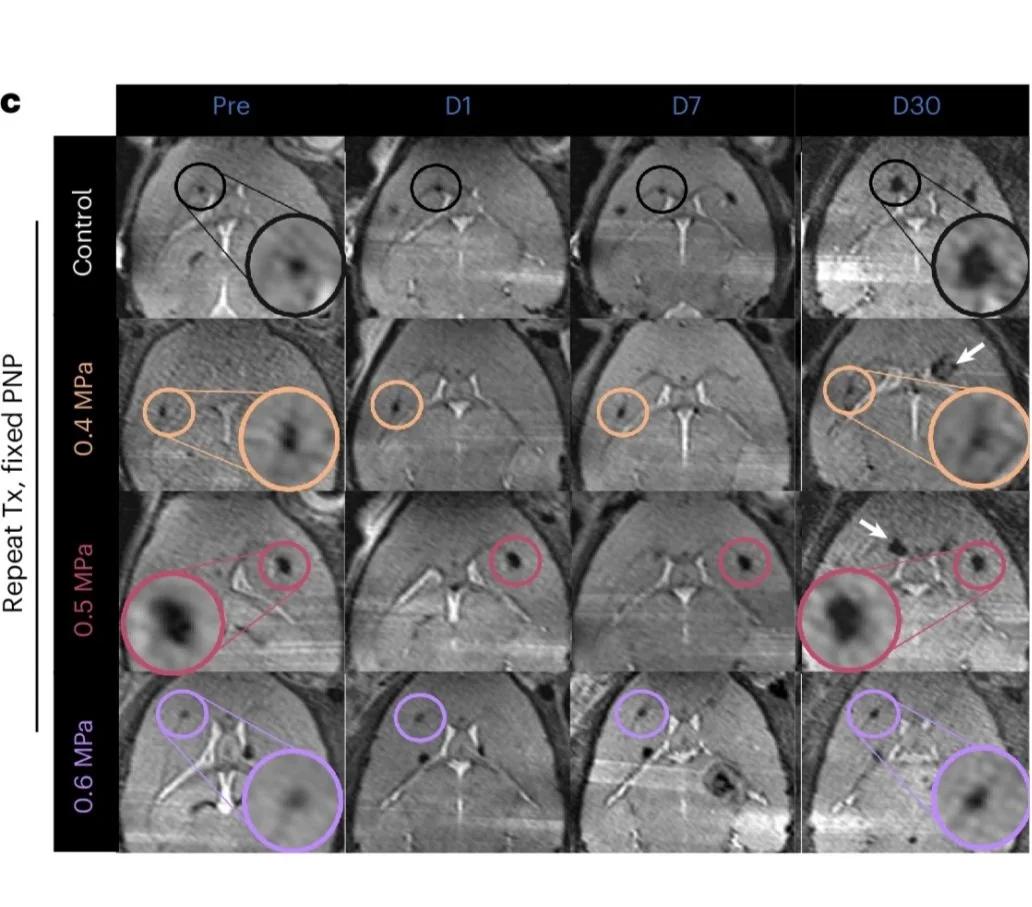

Focused ultrasound-microbubble treatment arrests the growth and formation of cerebral cavernous malformations

Nature Biomedical Engineering

Delaney G. Fisher, Tanya Cruz, Matthew R. Hoch, Khadijeh A. Sharifi, Ishaan M. Shah, Catherine M. Gorick, Victoria R. Breza, Anna C. Debski, Joshua D. Samuels, Jason P. Sheehan, David Schlesinger, David Moore, James W. Mandell, John R. Lukens, G. Wilson Miller, Petr Tvrdik & Richard J. Price